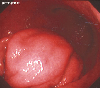

A case of an inflammatory tumor presenting as a gastric submucosal tumor.

Endoscopy

Inflammatory or ulcerative disease / lesions/Others